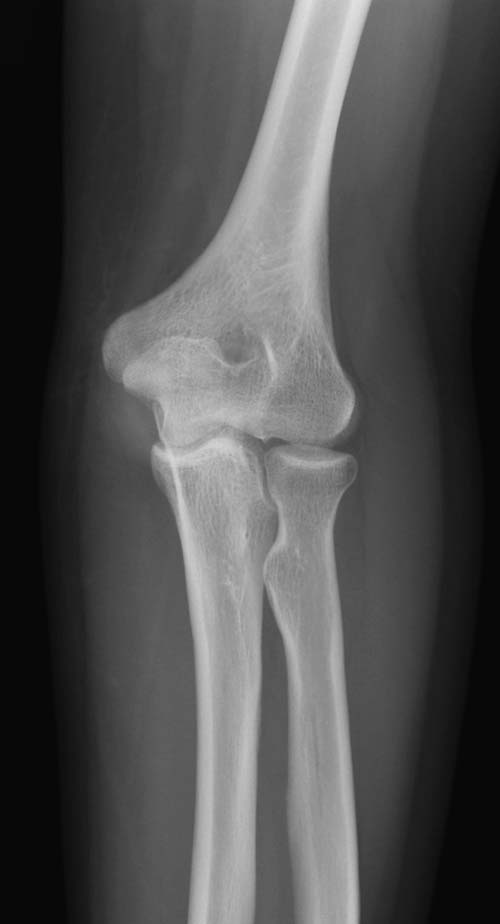

Обстоятельства дела. Пациентка Ш., 85 лет, поступила в отделение с оскольчатым переломом локтевого отростка с диастазом отломков. Из сопутствующей патологии: гипертоническая болезнь III ст.Б, АГ III ст, сахарный диабет, варикозное расширение вен н/конечностей, костный анкилоз левого локтевого сустава в порочном положении (после травмы более 30 лет назад). При более детальном осмотре рентгенограмм выявлен многооскольчатый перелом локтевого отростка с диастазом отломков, остеопороз (см. фото 1,2).

1) перелом - не оскольчатый, а раздробленный, с повреждением большей части локтевого отростка (С2 по А0, Тип IIIB по Mayo) с явлениями остеопороза, сминания промежуточных костных фрагментов. Подтверждением этому является наличие промежуточных костных фрагментов неопределенной формы, несоответствующей суставной части локтевого отростка, а также хорошо видимый передний подвывих костей предплечья (см. фото 2).

2) При раздробленных переломах локтевого отростка у пожилых людей до сих пор методом выбора является удаление проксимальных осколков локтевой кости и шов сухожилия трехглавой с дистальным отломком локтевой кости (см. Национальное рук-во «Травматология», 2008). Между тем, еще Каплан А.В. (1979) предупреждал, что «резекции локтевого отростка следует избегать в тех случаях, когда одновременно с переломом имеется вывих, так как после удаления локтевого отростка могут повторяться передние вывихи предплечья». Удаление локтевого отростка у данной пациентки добавило бы смещение предплечья кпереди к имеющемуся переднему подвывиху и привело бы к вывиху костей предплечья, и неблагоприятному функциональному результату. В связи с этим данный метод лечения было решено не применять. Напомню, что левая рука пациентки находится в положении костного анкилоза в локтевом суставе под углом 100°, и восстановление функции правой верхней конечности имело для пациентки принципиальное значение (качество жизни).